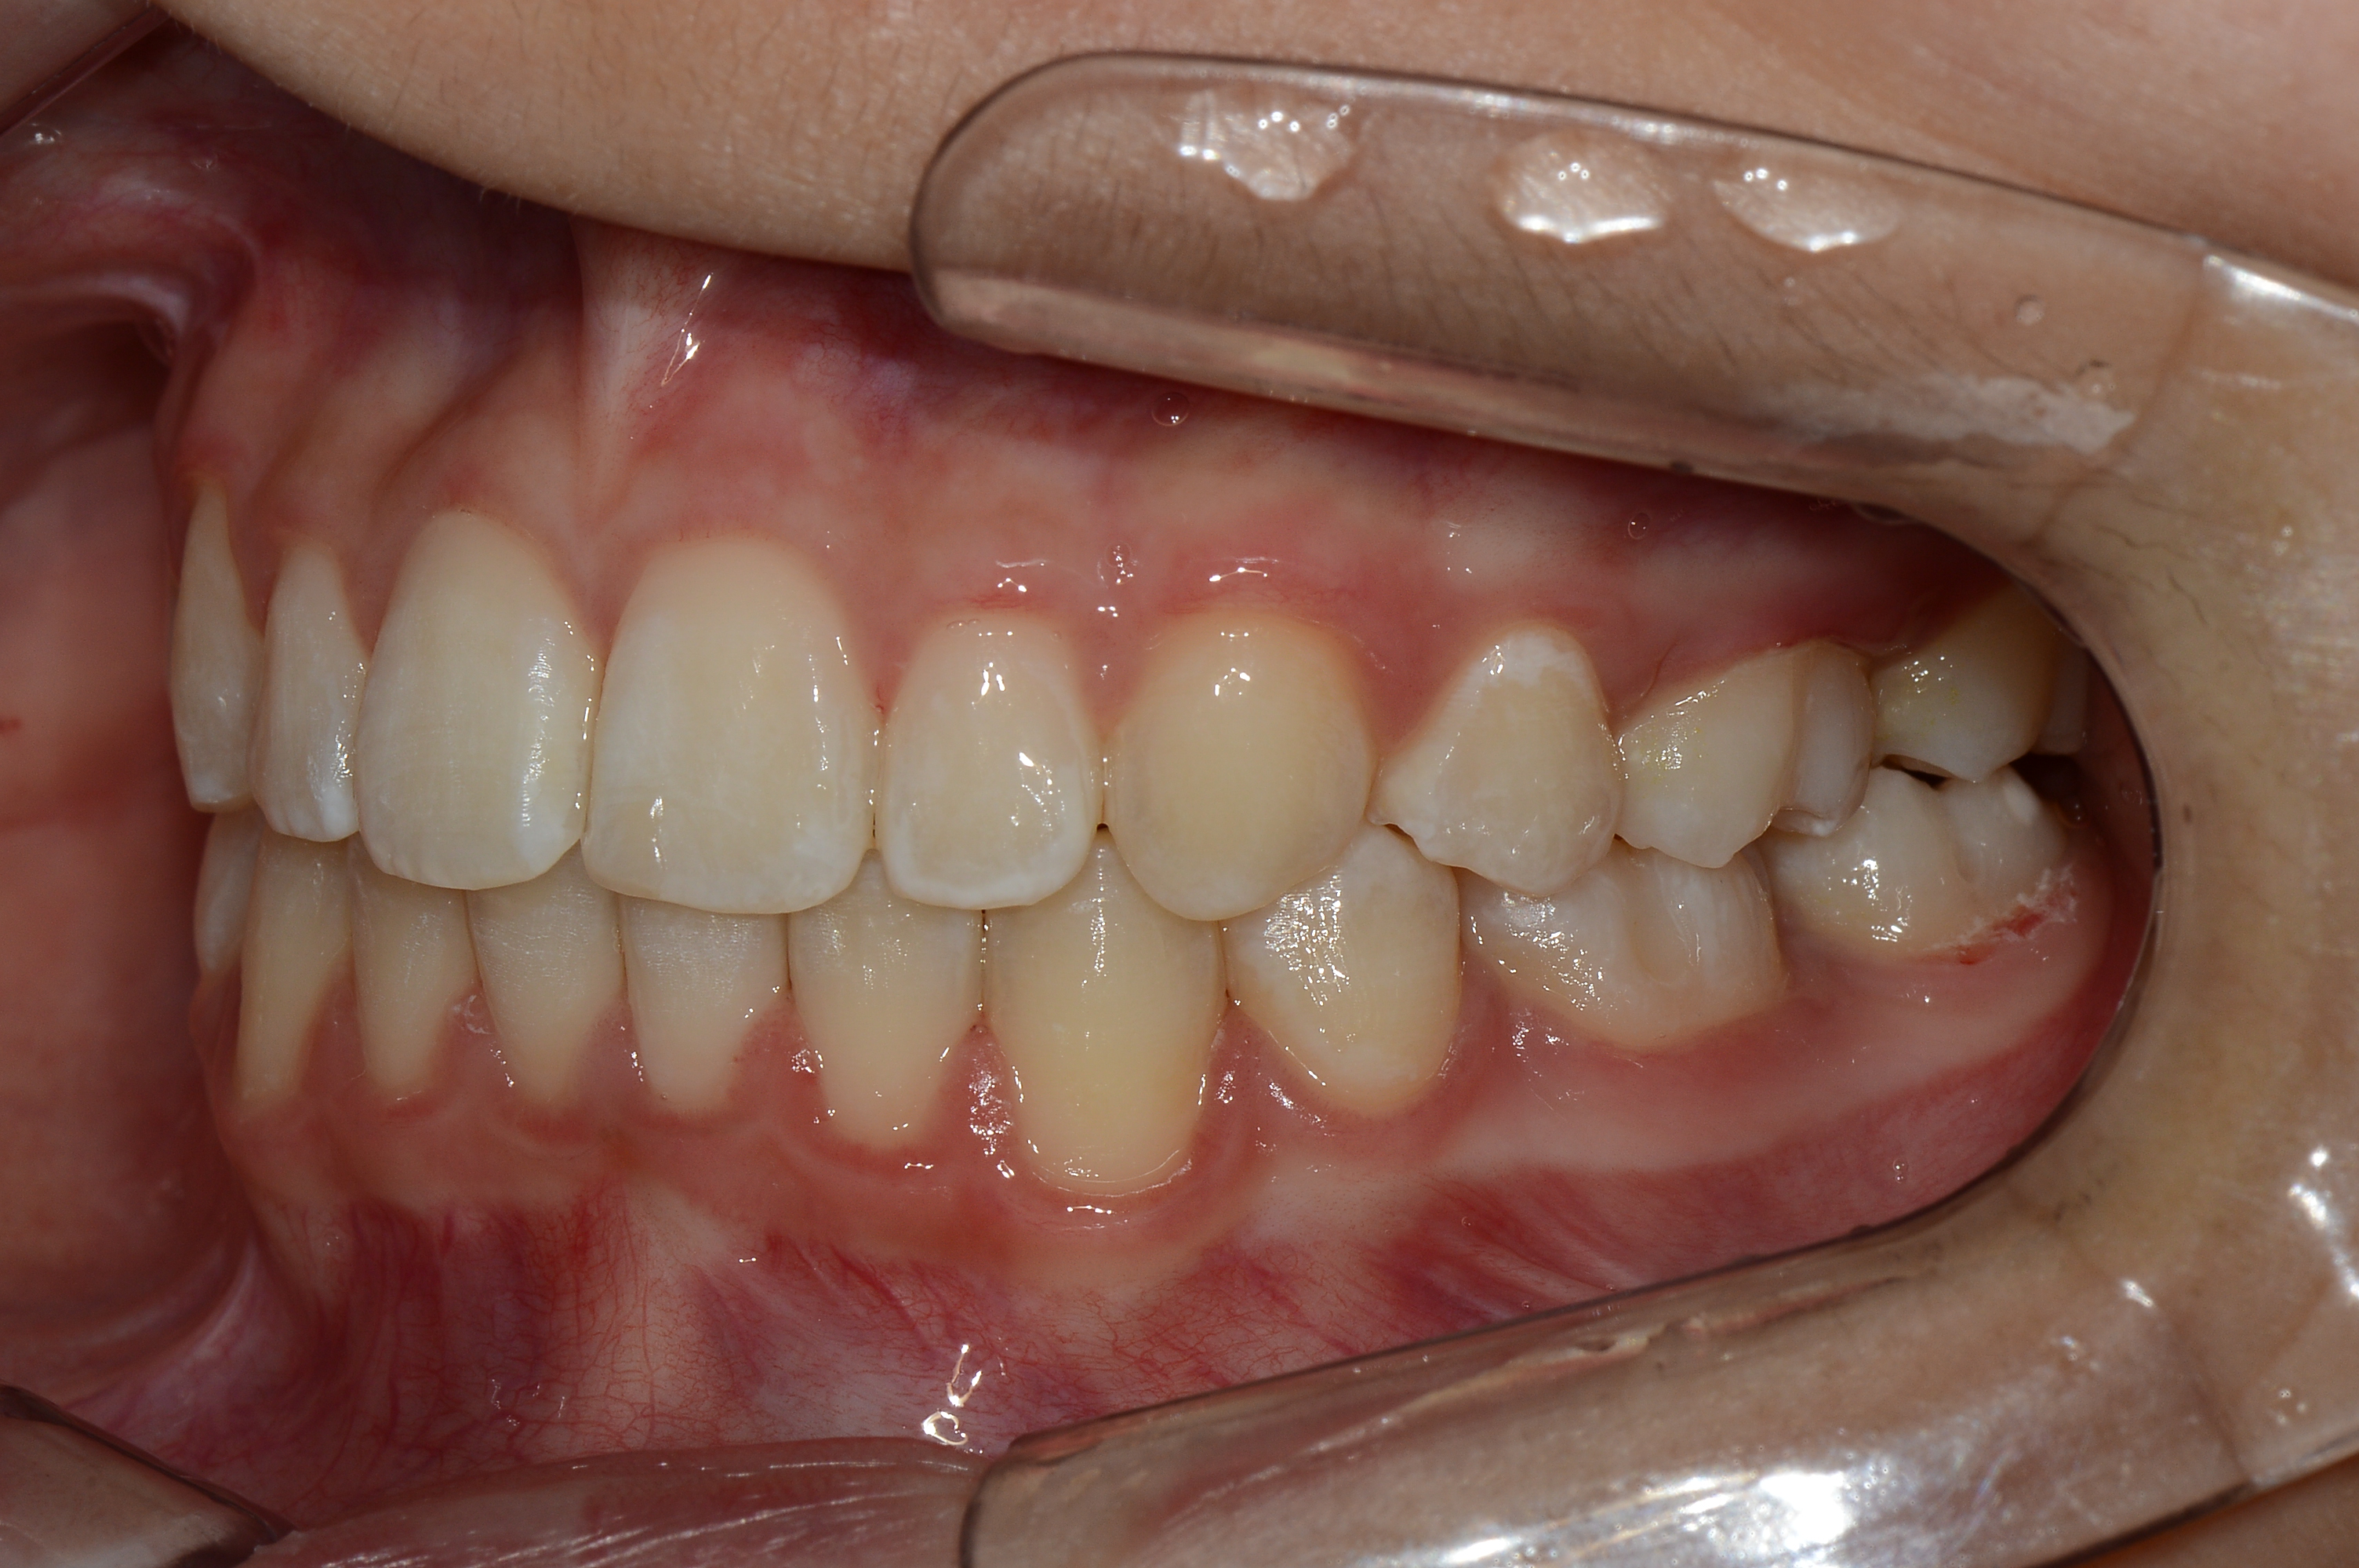

치료 후 사진입니다.